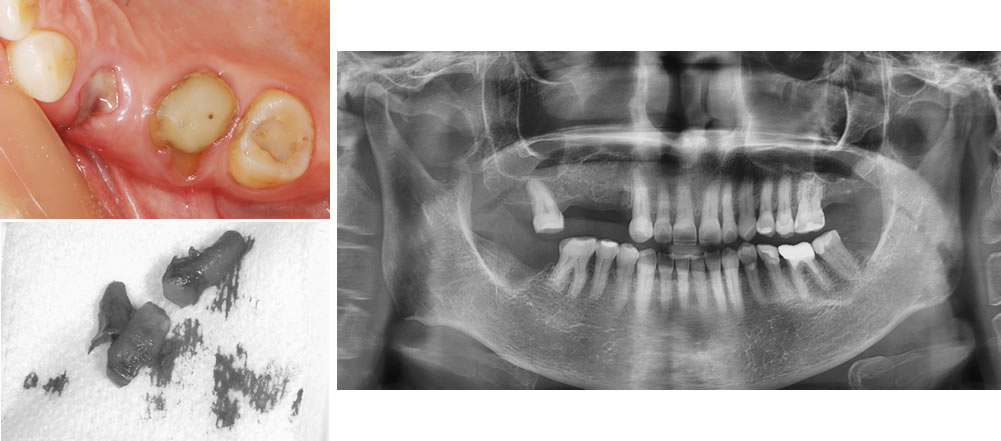

保存不可能な歯を抜歯

保存不可能な歯を抜歯し、歯茎と骨が治癒するまで待ちます。治癒を待っている間にセラミックの治療を行っていきます。

セラミック治療後および右上欠損部治癒後

抜歯を行なって6ヵ月経過した状態です。

入れ歯を作成するにあたって、歯を抜いた直後はまだ歯茎や骨の治癒が行われていないため、適合の良い入れ歯を作る事ができません。抜歯をした後の歯茎はボリュームが減少して形が変化していきます。

目安としては3ヵ月目までが大幅に変化し、6ヵ月目ぐらいまで微妙に変化していきます。しっかりと歯茎や骨の変化が落ち着いたタイミングで入れ歯を作成する事が適合の良い入れ歯を作成するためのポイントです。